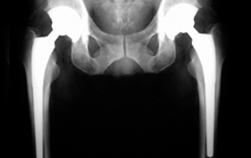

- 인공관절 수술 후 사진